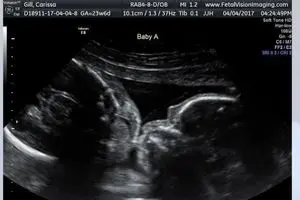

وقتی نوبت به سونوگرافی کاریسا در این مرکز تصویربرداری از جنین رسید، این زوج، شاهد صحنهای غیر عادی بودند. دوقلوهای…